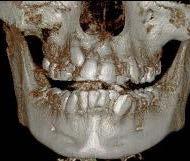

Estudios radiográficos de inicio

Al análisis radiográfico (Figura 3) se observa la clase II esquelética, patrón de crecimiento normodivergente, incisivo superior con adecuada inclinación respecto a su base ósea, incisivo inferior ligeramente proinclinado y vías aéreas permeables. En la radiografía panorámica (Figura 4) se ven 33 órganos dentarios OD, el infantil 53 presente en boca, el OD 13 impactado, los 37 y 47 en proceso de erupción y los terceros molares en formación.

En los cortes tomográficos, en el corte coronal (Figura 5) se muestra el OD 13 impactado y su proximidad con el incisivo lateral, en el corte sagital (Figura 6) grado de reabsorción radicular del OD 12.